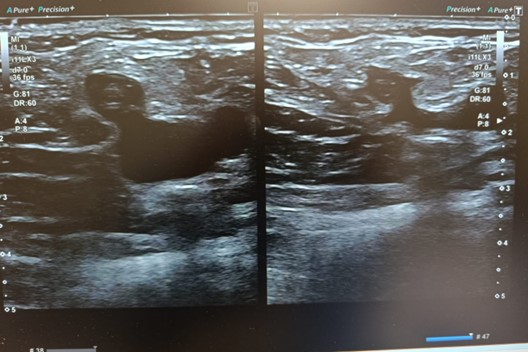

Ecografía Doppler

Ausencia de compresibilidad y material ecogénico compatible con trombosis en cayado de safena interna y externa, vena femoral superficial distal , vena poplítea y venas gemelares. Troncos tibioperoneos permeables.